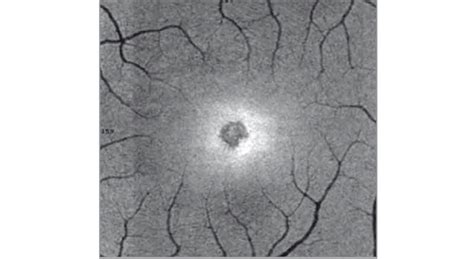

Eye damage from solar eclipse

Staring directly at the sun, even during a solar eclipse, can cause permanent eye damage. The sun's intense light can burn the retina, leading to vision impairment or blindness. Therefore, it is crucial to take necessary precautions to ensure safe viewing.